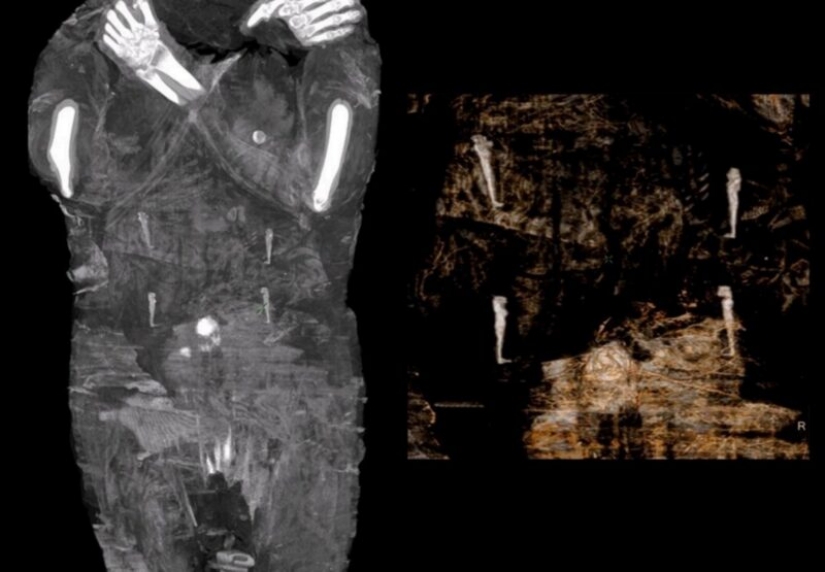

The Polish Academy of Sciences scanned all the ancient Egyptian mummies in local museums and made an interesting discovery. One of the mummies, which was previously thought to be a man, turned out to be a 20-year-old woman who was embalmed with a fetus inside.

A group of Polish scientists found out that an Egyptian mummy, which was previously thought to be a man, is actually a woman in the late stages of pregnancy. It appears to be the only known example of an embalmed pregnant Egyptian mummy.

For the new study, scientists decided to scan the body and were surprised to find that in fact, a woman in the seventh month of pregnancy is lying in the coffin.

According to scientists, this is the only known case of a well-preserved pregnant Egyptian mummy. They determined that the woman was between 20 and 30 years old. And the size of the fetal skull suggests that she was somewhere between 26 and 28 weeks pregnant.